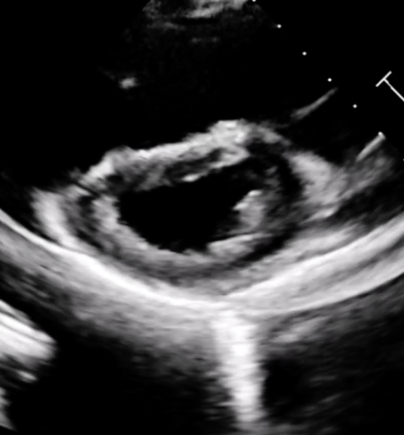

An 18-year-old female presented to the emergency department with acute-onset dyspnea, chest pain, nausea, vomiting, and syncope after four months of oral contraceptive use and active vaping. Physical examination revealed tachycardia (135 bpm) and tachypnea, with ECG showing sinus tachycardia. Laboratory studies demonstrated dramatically elevated D-dimer (12,756), elevated proBNP (660), and troponin (299 225). Echocardiography revealed the D-sign [Image 1] classic McConnell sign - severely dilated right ventricle with hyperkinetic apex and hypokinetic basal-to-mid free wall [Image 2], confirming massive PE with acute cor pulmonale. CT angiography revealed extensive bilateral pulmonary emboli with signs of right heart strain [Image 3]. Immediate anticoagulation with heparin was initiated, followed by ICU admission where alteplase was administered for massive PE. Remarkably, the patient demonstrated complete heparin resistance with no APTT response despite escalating doses over 24 hours and the decision was made to switch to rivaroxaban 15mg twice daily. Patient symptoms significantly improved on day 3 and was eventually discharged with follow up appointment to hematology.